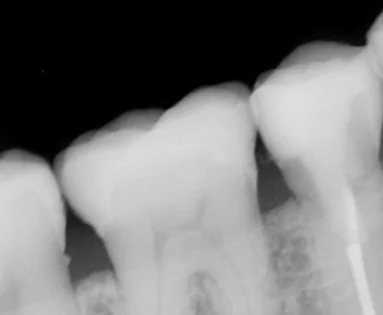

適合を確認するために撮影したレントゲンがこちらになります。

歯の亀裂で痛みが出たため、被せ物に。|坂寄歯科医院(取手市藤代) - 画像4

前後の歯に歯石がついているのが気になるところではありますが・・・

適合自体は問題なく、綺麗に隙間なく入っているのがわかるかと思います。 仮歯の時点で噛んだ時の痛みは消えていたので、安心してセラミックに出来ましたね。